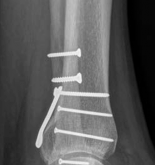

The fibula is approached through a direct lateral incision. The fracture is anatomically reduced, temporarily reduced with a point-to-point reduction (Weber) clamp, and fixed with two independent screws (Fig 2.3-3). A plate may be used as per surgeon preference.

Fig 2.3-3a–b Immediate postoperative x-rays showing an anatomical ankle mortise achieved using a combination of posterior buttress plate and lag screws.